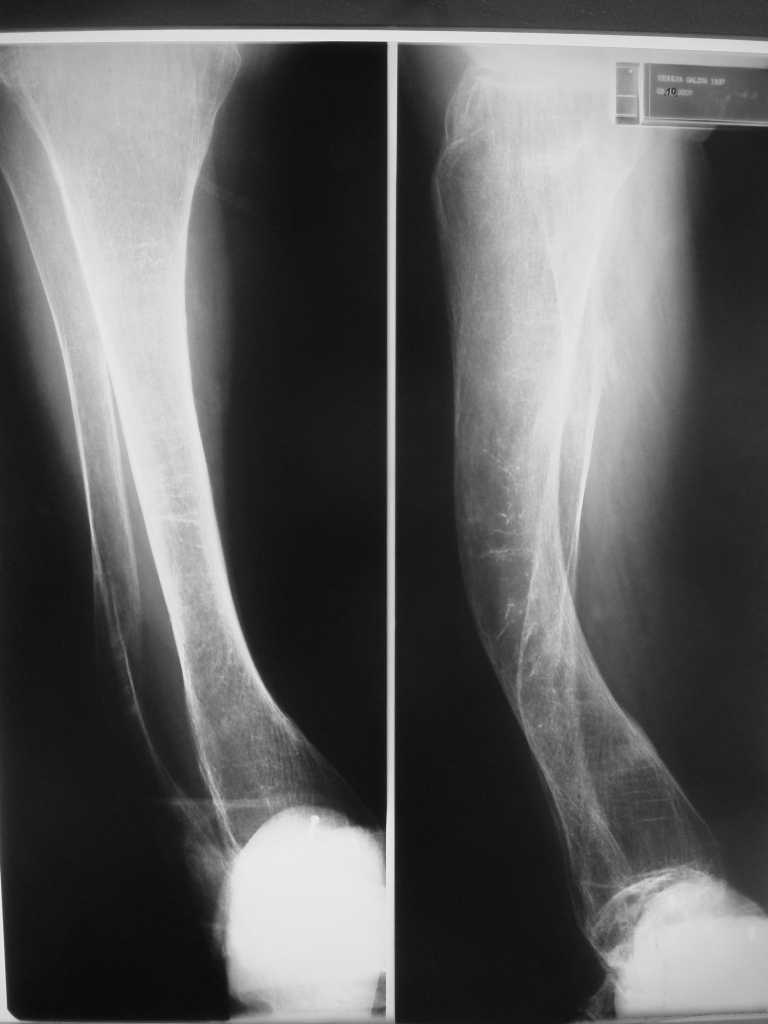

Контрольные рентгенограммы прилагаю.

Проблема в том, что в сагитальной плоскости угол голеней =30 градусам. Ширина канала 30.

ДС> Проблема в том, что в сагитальной плоскости угол голеней =30 градусам. Ширина канала 30.

Если при введении стержня будет видно, что из-за искривления дело идет к перфорации стенки, надо будет сделать чрескожную остеотомию на уровне кончика стержня.

ДС> Будет ли остеосинтез стержнем стабильный?

Во-1-х, интрамедулярный остеосинтез относится к методам, дающим относительную, не абсолютную стабильность. Во-2-х, стабильность неплохо обеспечивается запирающими винтами. В-3-х, несоответствие кривизны стержня и канала приводит к повышению стабильности, в-4-х, канал можно искусственно сузить введением отклоняющих (трансмедуллярных, Poller) винтов.